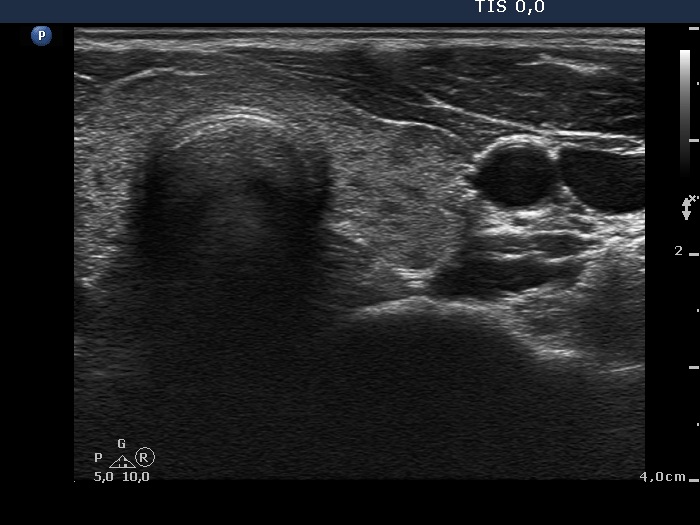

Follow-up examination 15 months after first visit (third row of images):

Clinical presentation: The patient was regularly followed-up and was euthyroid on daily 10 mg methimazole. She had no complaints.

Palpation: no abnormality.

Results of blood test: euthyroidism on daily 10 mg methimazole (TSH 1.83 mIU/L, FT4 14.6 pM/L).

Ultrasonography: The thyroid was echonormal and contained small hypoechogenic areas. The vascularization was practically absent.

The thyrostatic was discontinued.